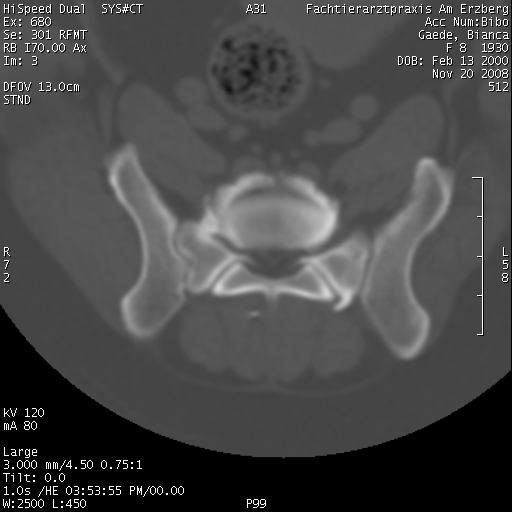

Bezüglich des CT, da ist einfach der große Vorteil, dass man auch Probleme der Knochen sehen kann, die eventuell zu klein sind oder nicht genau genug auf dem Röntgenbild.

Mal als Vergleich